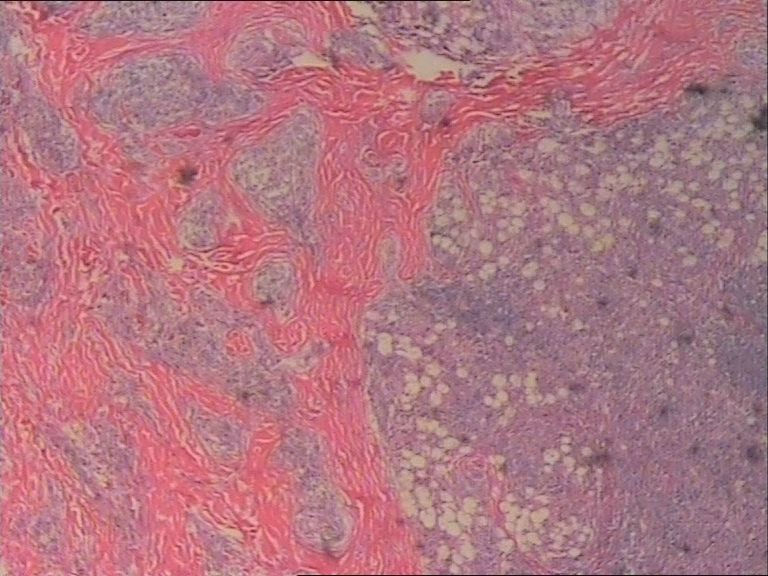

患者    女    47岁    腰部皮下肿块5x4cm,皮肤表面灰褐色,无隆起,无压痛。体格检查无其他异常。

是的,拿来给大家看的主要原因是本病细胞学比组织学特征更明显。

图片很清晰,挺好,就是看不明白,好像就是很多的多核巨细胞和炎细胞?似乎还有真菌菌丝似的东西?似乎是个肉芽肿病变,还得做活检手术吧?

单核及多核组织细胞是本病不特异但恒定的特点,可惜高倍镜图片看不清核结构,显微镜下很清楚。

纤维黄色瘤

最后诊断为Rosai-Dorfman病。